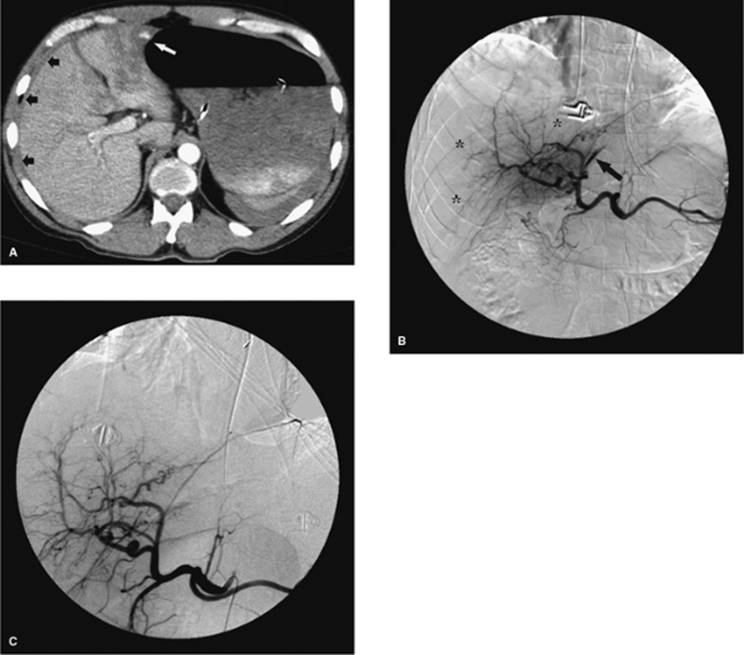

Hepatobiliary Drainage

Whereas percutaneous biliary interventions gained popularity in the 1970s and 1980s, the development of endoscopic retrograde cholangiopancreatography (ERCP) has largely replaced the percutaneous approach for many disease states. However, the technique of choice will mainly depend on the skills available by physicians at the local institution (28). Additionally, there are instances where a percutaneous approach is preferred over an ERCP, mainly instances where ERCP fails, or ERCP is not an option due to prior intestinal surgery that does not allow the endoscope to reach the biliary tree (Figs. 35.14 and 35.15).

Prior to the initiation of the procedure, any coagulopathy should be corrected and prophylactic antibiotics administered. Preprocedure imaging includes either a CT scan, ultrasound, or magnetic resonance imaging (MRI) to look for the location of dilated bile ducts and also to evaluate the anatomy of the liver. The right upper quadrant of the abdomen in the midaxillary line is prepped, using sterile technique, for an intercostal approach. Although the right-sided approach is commonly used, many interventional radiologists prefer to access the biliary tree via a left-sided ductal approach.

After conscious sedation is administered, a 22-gauge needle is advanced into the liver using fluoroscopic guidance. Diluted contrast is injected as the needle is slowly withdrawn; alternatively, the needle can be advanced and contrast injected. This technique works well for the nondilated system. After identifying the biliary system, further contrast is injected slowly to opacify the biliary tree and identify a suitable access site in the bile ducts. Next, with the contrast-filled duct as a target, the system is entered using a 22-gauge needle with fluoroscopic guidance. Thereafter, there are two options. First, an external drain can be placed to decompress the system, with the patient being brought back to the interventional radiology (IR) suite 24 hours later; this reduces the risk of introducing infected bile into the bloodstream. The second option is to attempt internal/external drainage. Although this may save the patient one step in a staged procedure and allow for physiologic drainage of bile, there is a risk of introducing infection as previously described. It is the authors' preference to achieve external drainage first and allow the ducts to drain overnight before attempting any lengthy intervention (Figs. 35.16 and 35.17).

000431

Figure 35.14. Failed endoscopic placement of common bile duct (CBD) stent due to the presence of a large mass (black arrow) within the CBD. (Image courtesy of James Caridi, MD.)

000434

Figure 35.15. Successful percutaneous drainage using a left-sided biliary duct. Note that the drainage catheter has been advanced past the obstruction and into the small intestine. (Image courtesy of James Caridi, MD.)

000439

Figure 35.16. Patient presents with biliary obstruction. On hospital day 1, external drainage has been achieved using a right-sided bile duct approach. Cholangiogram shows complete obstruction in the mid common bile duct (CBD) (black arrow).

000443

Figure 35.17. On hospital day 2, internal/external drainage has been achieved by gaining access to the small intestine across the area of obstruction.

000250

Figure 35.18. This is the same patient as in Figures 35.16 and 35.17. A metallic self-expanding stent has been placed across the area of obstruction in the distal common bile duct. Note the waist in the stent (black arrow) due to the surrounding mass.

000446

Figure 35.19. Post–stent placement and balloon angioplasty. No residual stenosis is noted, and the stent is fully expanded.